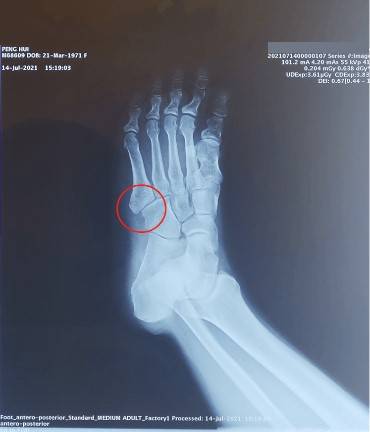

正常儿童骨骼解剖 -右第五跖骨基底部骨骺误为骨折

图1x线示第五跖骨近端骨骺增大,碎裂,骨与软骨交界处增宽(红色圈所指)